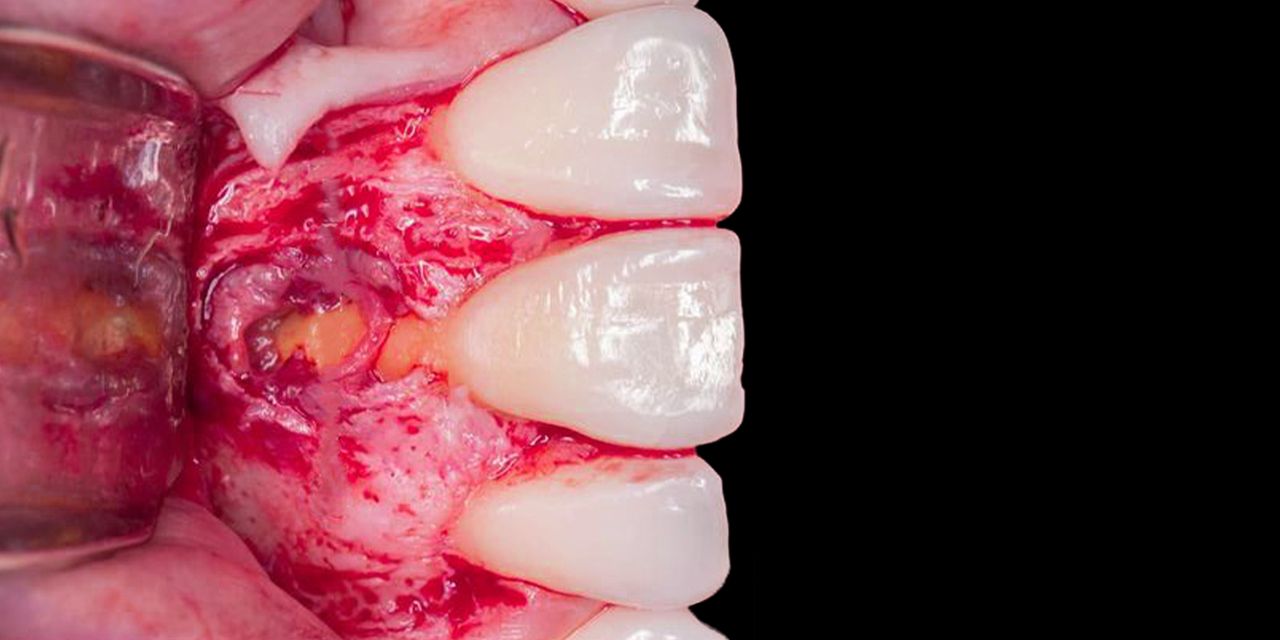

Ретроградное пломбирование: материалы. Биокерамика

– Показания к эндодонтической хирургии

– Материалы для ретроградного пломбирования корневых каналов

– Факторы, влияющие на результаты хирургических процедур в эндодонтии

– Преимущества современных микрохирургических методик

– Ультразвуковые приборы в эндодонтической микрохирургии

– Ретроградное пломбирование: требования к материалам

– Свойства материалов для ретроградного пломбирования:

- Амальгама

- СИЦ и их модифицикации для ретроградной пломбировки

- ЦОЭ цемент и Super EBA

- МТА

- Биокерамика.

– Инструменты для ретроградной пломбировки корневых каналов

– Биоактивность и биосовместимость биокерамических материалов

– Ленточная перфорация зуба: протокол лечения

– Гистологические аспекты заживления тканей после апикальной хирургии

– Методика внесения и компакции материала при ретроградной пломбировке

– Экстраоральная резекция верхушки корня:

- Показания

- Техника

- Клинические рекомендации.